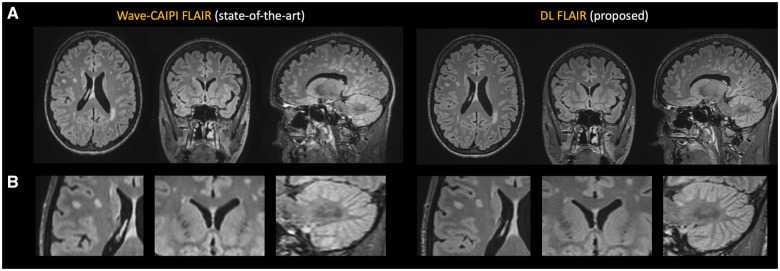

Purpose: To evaluate the diagnostic quality and interchangeability of DL-based 3D FLAIR with a state-of-the-art acceleration technique (wave-controlled aliasing in parallel imaging [Wave-CAIPI] FLAIR) in a clinical setting with 3 T brain MRI.

Results: Totally, 88 participants (61 women [69%], 47 ± 13 years) were evaluated. DL-FLAIR reduced scan time (1:53 vs. 2:50) and showed higher overall image quality, anatomic conspicuity, lesion conspicuity, and imaging artifacts compared with state-of-the-art technique (all Ps < .001). DL-FLAIR also demonstrated higher signal-to-noise ratio and contrast-to-noise ratio compared to Wave-CAIPI-FLAIR, with high agreement in lesion and regional brain volumes between both methods (ICC(2, k) range, 0.91 to 0.99). DL-FLAIR proved interchangeable with Wave-CAIPI-FLAIR for lesion count (IEI: 0.10, acceptable proportion: 0.977, 95% CI: [0.943, 1.000]) and for lesion volume (IEI: 0.32, acceptable proportion: 0.966, 95% CI: [0.930, 1.000]).

Conclusion: Deep learning reconstruction of 3D-FLAIR provides higher image quality compared to a state-of-the-art technique with 30% less scan time while maintaining excellent agreement and interchangeability in quantitative evaluation.